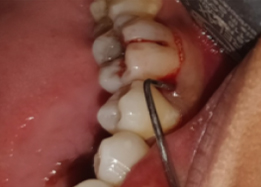

Hemisectomy

PRE OP Clinical Photograph Measuring Probing Depth